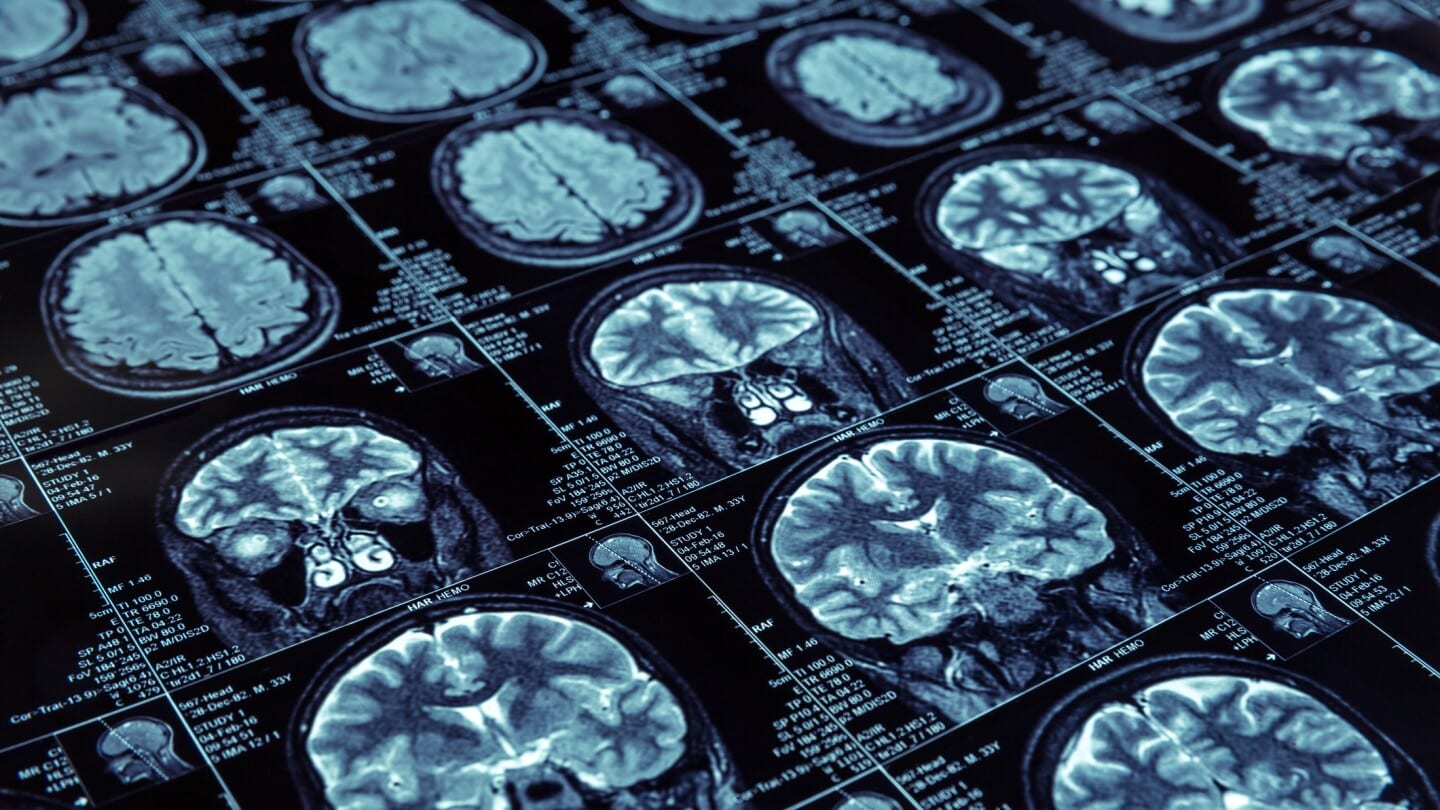

The APOE4 gene variant has long been associated with an increased risk of Alzheimer’s disease and complications from treatments like Biogen and Eisai’s Leqembi. The European Medicines Agency has even deemed patients who are homozygous for APOE4 ineligible for this groundbreaking therapy due to concerns about amyloid-related imaging abnormalities (ARIA). However, Eisai recently presented data indicating that the incidence of ARIA events in homozygous patients may be lower than previously reported. Their analysis showed that only 21.2% of APOE4 homozygotes experienced ARIA, compared to 13.7% of noncarriers, with most cases being asymptomatic.

In the context of treatment efficacy, Eisai reported that 76% of patients with two copies of APOE4 maintained or improved their disease stage after treatment. This finding suggests that the benefits of Leqembi may outweigh the risks, particularly if patients are treated earlier in the disease process. Eisai’s chief clinical officer, Lynn Kramer, emphasized the importance of understanding these risks to encourage earlier treatment initiation for homozygous patients. The company plans to continue gathering real-world data to potentially revise treatment guidelines for APOE4 homozygous patients.

Alzheon has also made strides in Alzheimer’s research, particularly with its candidate drug, valiltramiprosate. The company presented new data at the AD/PD meeting, highlighting the drug’s potential benefits for patients with mild cognitive impairment (MCI). Previous trials indicated that valiltramiprosate might be particularly effective for those carrying the APOE4 variant, a population that faces significant unmet medical needs due to treatment restrictions. Alzheon’s chief scientific officer, John Hey, noted that the drug has shown a sustained reduction in p-tau-217 levels, a biomarker linked to amyloid pathology, over four years of follow-up.

Importantly, Alzheon’s Phase 3 study revealed no significant difference in ARIA-E rates between the treatment and placebo groups, and even lower rates of ARIA-H in those receiving the drug. This suggests that valiltramiprosate may mitigate some of the risks associated with other Alzheimer’s treatments. Looking ahead, Alzheon plans to conduct further studies to confirm these findings and aims to position the drug as an early intervention for patients showing initial symptoms of Alzheimer’s. The integration of fluid biomarkers into treatment strategies could enhance precision medicine approaches in Alzheimer’s care, providing physicians with better tools for patient management.